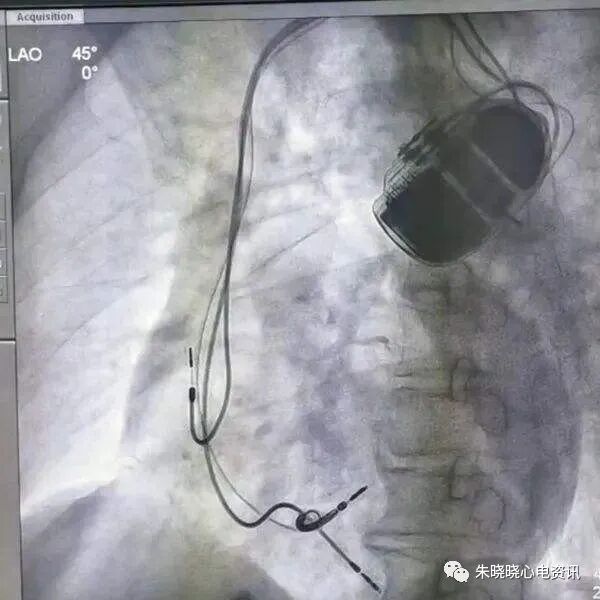

百多力起搏器接线部分和餐桌上的碗筷组合相似(图11)

图11 百多力起搏器

百多力起搏器怎么样“贴心”的通过胸片识别起搏器方法,让你秒懂_https://www.jmylbn.com_新闻资讯_第13张